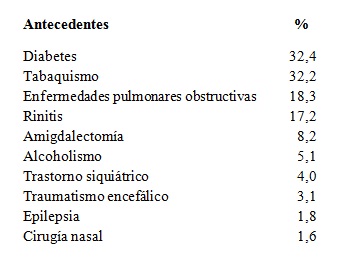

Otras enfermedades frecuentes fueron: diabetes (32,4%), tabaquismo (32,2%), enfermedades pulmonares obstructivas (18,3%) y rinitis (17,2%) (Tabla 7).

Se relevó la cantidad de pacientes que recibían en forma permanente medicación con posible efecto sobre el sistema de control de la respiración. Se incluyeron: sedantes e hipnóticos, antidepresivos, relajantes musculares, antialérgicos, hormonas de reemplazo y antisicóticos (Tabla 8).